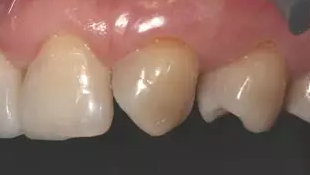

術(shù)后上前牙正面照

病例分享|復(fù)合樹脂微創(chuàng)美學(xué)修復(fù)關(guān)閉上前牙間隙

術(shù)后上前牙右側(cè)面照